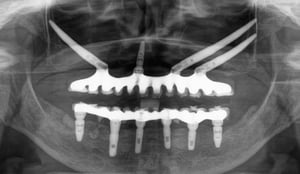

Uz pomoć naprednih kirurških tehnika i posebnih zigomatičnih, pterigoidnih, transnazalnih, subnazalnih i transsinusnih implantata, IMED Full Arch Concept® omogućuje fiksno protetsko rješenje čak i za slučajeve s potpunim gubitkom kosti čeljusti.

Koristimo posebne zygoma, pterigoidne, transsinusne i transnazalne implantate koji se sidre u čvrste koštane strukture izvan zubnog grebena. Tako je moguće ugraditi fiksni most čak i kod izrazito resorbiranog grebena, bez klasične nadogradnje kosti.

IMED Full Arch Concept® temelji se na digitalnim CBCT snimkama, intraoralnom skeniranju i CAD/CAM tehnologiji. To omogućuje precizno planiranje položaja implantata i izradu mosta koji je prilagođen vašem licu, zagrizu i osmijehu.

Sam zahvat traje otprilike 2 do 3 sata i izvodi se pod općom (potpunom) anestezijom, pa je za pacijenta u potpunosti bezbolan. Iskusni tim specijalista oralne kirurgije, subspecijaliziran za najteže implantološke operacije, prema digitalnom planu postavlja odabrane implantate u čvrste koštane strukture kako bi osigurali maksimalnu stabilnost.

Nakon ugradnje implantata, u kratkom roku (najčešće unutar 24 sata) postavlja se privremeni fiksni most učvršćen na implantate. Pacijent dobiva funkcionalne, fiksne zube koji omogućuju normalno žvakanje, govor i svakodnevno funkcioniranje tijekom razdoblja cijeljenja implantata.